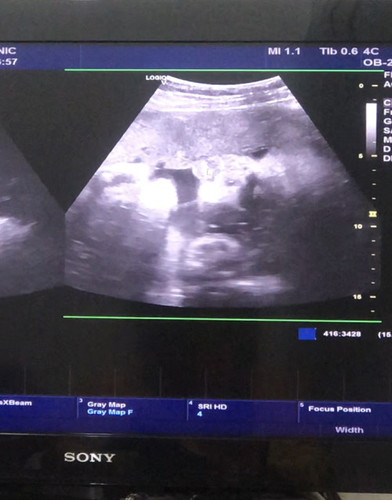

32สัปดาห์5วัน น้องหนัก1924 เเม่ๆว่าน้ำหนักน้องน้อยไปไหมคะ 🥺

กำลังดีค่ะแม่ ของเรา32+5 1940กรัมค่ะ หมอบอกว่าอยู่ในเกณฑ์ดีเลยค่ะ

ของเรา 32วีคตรง 1825เองค่ะ ใกล้คลอดเอาให้ได้ 2500ขึ้นก็พอแล้วค่ะ มาโตข้างนอกเอา🥰

บ้านนี้ 37+3 ได้แค่2180 เองค่ะ หมอบอกน้องไม่รับสารอาหาร🥲🥲

ทีมตุลาเหมือนกันคะน้ำหนักน้อง1850กรัมเองคะ